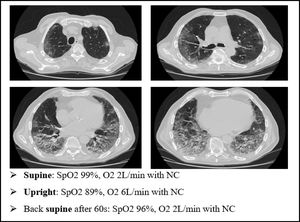

This mechanism is well represented in Fig. 4, a 49yo male with no past medical history. The CT scan was obtained after 9 days from the onset of symptoms, and displays the typical radiological findings of SARS-CoV-2 pneumonia, mainly in the dorsal region of the lungs. Visual severity score was 12/20. This was one of the patients that underwent lung biopsy. Lung tissue from the altered region of the right lower lobe showed areas of high blood flow, due to capillary hyperplasia and venous dilation, surrounding patent alveoli. Switching the patient to the prone position resulted in a rapid improvement in arterial blood oxygenation at ABGs.

We present an explanatory case as seen in our ward (Fig. 7). This is an 80 yo male, former smoker, with a past medical history of arterial blood hypertension and benign prostatic hypertrophy. He was admitted in to our Semi intensive Respiratory Care Unit for SARS-CoV-2 pneumonia and treated with CPAP for several days. After the weaning from CPAP, the patient started to develop clinical signs of platypnea orthodeoxia. As shown in Fig. 4, he needed a relatively small amount of oxygen through nasal cannula (NC) to maintain a normal level of SpO2 while lying down. However, sitting up resulted in a drastic drop in SpO2 levels, requiring increase in O2 flow.

The patient underwent a CT scan. It was 18 days since the onset of symptoms. The CT scan showed bilateral ground glass attenuation, crazy paving and consolidation, especially in the lower lobes.

Moreover, the vascular enlargement is usually more represented in the lower regions of the lungs, leading to a sudden increase in perfusion of the dependent areas of the lung as soon as the patient stands upright. This overflow causes further reduction in V/Q ratio, hence a swift worsening of hypoxemia in sitting position (Fig. 8).41

We can speculate a similar mechanism in type L COVID-19 patients showing platypnea orthodeoxia. The main histopathological feature of SARS-CoV-2 pneumonia is vascular enlargement, therefore if the COVID-19 lesions are more severe in the lower areas of the lungs (as in Fig. 7), it is possible for the patient to develop the platypnea orthodeoxia syndrome, with the same mechanism of HPS.